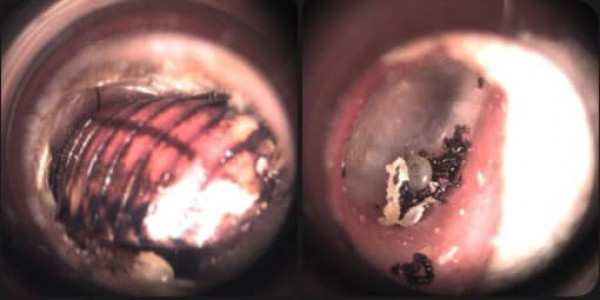

ล่าสุดพบผู้ป่วยเด็กกำลังไปรับประทานอาหารในร้านอาหารแห่งหนึ่ง ถูกแมลงเม่าบินเข้ารูหู และรู้สึกเหมือนมีแมลงไต่ข้างในหู ผู้ปกครองจึงรีบพาเด็กมาพบแพทย์ ด้วยความโชคดีที่เด็กอยู่ในเมือง ใกล้โรงพยาบาล จึงพบแพทย์และทำการรักษาได้ทัน และนำแมลงออกจากหูได้อย่างปลอดภัย

"ขี้หู" ในแต่ละคนจะแตกต่างกัน ขี้หูบางคนมีลักษณะเหนียว เหลือง พบในผู้ที่มีผิวมัน บางคนขี้หูแข็งเหมือนก้อนหิน ดังนั้น ควรสังเกตขี้หูของตนเองว่ามีลักษณะที่ปกติหรือไม่ หากมีขี้หูออกมาเป็นสีเขียวปนเลือด หรือมีลักษณะเป็นเชื้อรา ที่มีลักษณะเหมือนทิชชู่เปียกน้ำ ให้รีบพบแพทย์เพื่อทำการรักษาอย่างถูกต้อง” ผศ.นพ.จารึก หาญประเสริฐพงษ์ กล่าว